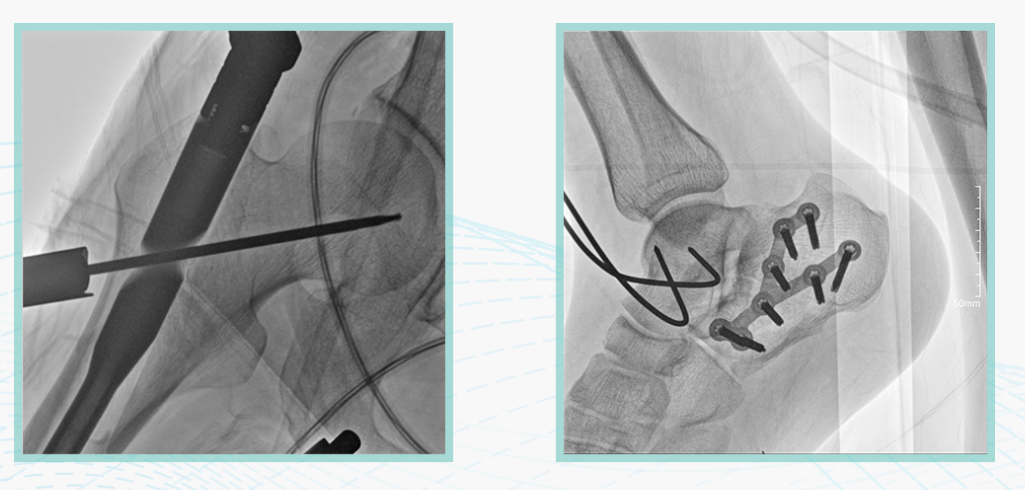

广东会科技悦画移动C臂X线摄影系统,采用了业内技术最尖端的CMOS探测器。基于性能优异的针状CSI闪烁体涂层和高灵敏度的CMOS感光芯片,悦画可以实现在超低X线剂量条件下实现高清晰影像成像,相较于一般的影增移动C臂和平板C臂,动态范围更高,影像的层次感和对比度更好。

在产品的性能参数设计上,悦画的像素可达到200万,空间分辨率可达到3.2线对,采用16bit的影像灰度,悦画在影像后处理上,通过SPI金字塔图像算法,支持摄影、脉冲透视影像、连续透视等多种模式下的影像采集,动态透视影像视频支持保存与回放。双大屏的设计,透视影像支持三档放大,保证临床影像读取的便利。

悦画在影像的伪影处理上,也积累多项图像处理专利技术。通过对植入物的精准识别,悦画能够精准祛除植入物伪影与运动伪影,保证高质量的影像输出,无论是影像的对比度、分辨率(清晰度)相较于市面上的移动C臂产品都更胜一筹。